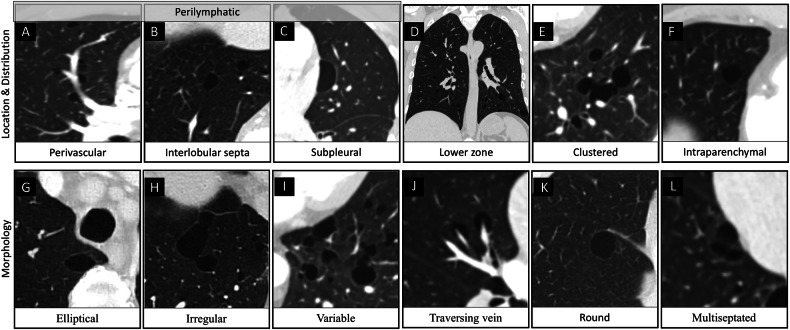

Results: Of 1475 patients with RN, 127 (8.6%) had PCs; 40 underwent genetic testing (median age 56 [49-68], 28 men), and 6/127 (4.7%) individuals tested positive for BHDS. BHD+ had significantly more and larger cysts, affecting more lobes (p < 0.01). Higher prevalence of PCs with a perivascular (100% vs. 37%; p = 0.01) and interlobular septal location (100% vs. 16%; p < 0.001), and perilymphatic distribution (100% vs. 5%; p < 0.001) was found in BHD+. All BHD+ had elliptical, irregular, and variable shape PCs, compared to a lower prevalence of these in BHD- (p < 0.01). Traversing vein sign was more common in BHD+ (83% vs. 24%; p = 0.01). The highest accuracy was achieved for perilymphatic distribution (97%), followed by irregular shape (94%) and interlobular septal location (91%).

Key points: Birt-Hogg-Dubé syndrome (BHDS) should be considered in patients with renal neoplasms and multiple pulmonary cysts. A lower zone predominant, perilymphatic distribution of pulmonary cysts is a strong indicator of BHDS. Identifying specific CT features of pulmonary cysts can improve recognition of BHDS.